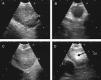

Hyperechogenic density in the interior of the LN (Figs. 1 and 2).

Fig. 1.Series of EBUS images of the mediastinal lymph node showing the different criteria: (A) heterogeneous echogenicity with a distinct margin in a reactive lymph node. (B) Homogeneous echogenicity with an indistinct margin in a reactive lymph node. (C) Heterogeneous echogenicity with a distinct margin in adenocarcinoma. (D) Hyperechogenic density in the interior of a lymph node (arrow) in small cell carcinoma. The lymph node images (A–D) show the absence of central hilar structure.